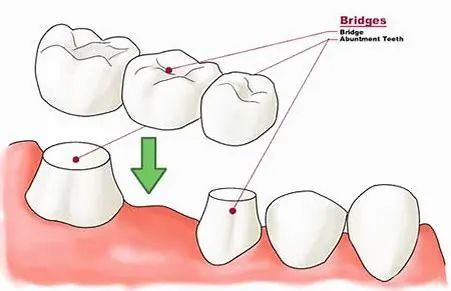

02 - 固定局部义齿

又称为固定桥,由固位体(A)和桥体(B)、连接体(C)组成。暂且可以把拔牙的地方想象成一条河,修复它就相当于建一座桥,那么桥墩就是缺失牙两侧的牙齿,套在桥墩上的部件称为固位体,桥体就是缺失牙位置的修复体。

为了让桥墩能够套入固位体内(A)和桥体(B)形成一个整体,我们需要对桥墩进行改造(牙体预备),部分位置倾斜的桥墩在预备前可能还需要根管治疗,然后再利用粘接剂将固定桥粘接在预备后的桥墩上。

固定桥修复一般需要在拔牙后3个月进行,治疗时长一般在1个月内,医患双方沟通好方案后,开始选择颜色、牙体预备、制作牙齿的模型、做临时牙、送加工厂制作、戴牙。

固定桥的材料主要是全瓷冠和烤瓷冠,后者内层衬有金属,价格较前者便宜,但容易出现牙龈着色的情况。

向左滑动查看固定义齿修复,慎滑(图片来源于必应)

「适应症」:固定桥的设计和制作较活动假牙复杂更多,考虑因素颇多,包括口内其它牙的健康情况、缺牙数目和部位、患者的咬合关系等等,因此建议找专业的修复医生求诊。

「注意事项」:烤瓷冠由于内层金属的存在会影响身体其它部位放射学检查成影;不建议用来咬硬物;定期随访确保基牙健康。

「优点」:不用摘取,美观程度较高,没有明显异物感,咀嚼效率更高。

「缺点」:需要对缺失牙两侧的牙齿进行磨除预备;根据材料不同,费用不同,一般高于活动义齿;烤瓷冠会使牙龈着色。